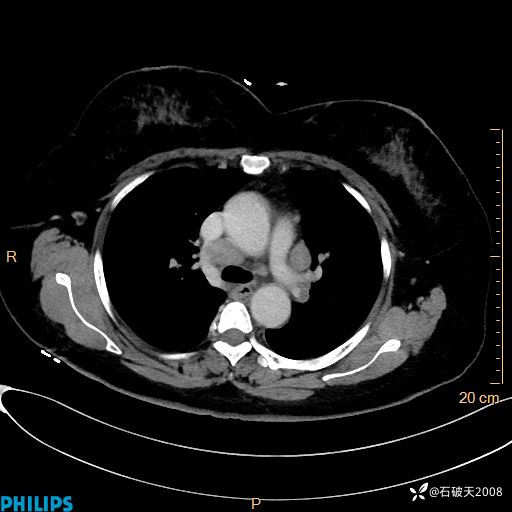

肺结节病?纵膈型肺癌?淋巴瘤?有点意思,欢迎围观

女 52岁 主 诉:咳嗽10余天,咳痰2天。

现病史:10余天前无明显诱因出现咳嗽,呈阵发性干咳,伴咽喉部发痒,无咽痛,无咳痰,无鼻塞、流涕、打喷嚏,无发热、畏寒、寒颤,无头痛、头晕,无胸闷、胸痛,无反酸、烧心,无腹痛、腹泻,无尿频、尿急,无皮疹等,在当地诊所求治,给予口服药物治疗(具体不详),病情无好转。遂在当地社区卫生服务中心开具口服药物治疗(具体不详),疗效欠佳。2天前出现咳痰,在我院门诊求治,行胸部CT提示肺部感染,建议住院,患者要求口服药物治疗,目前仍咳嗽、咳白色粘痰,白天量多,夜间自觉喉部喘鸣音,遂再次来院就诊,以“肺部感染”为诊断收入院。发病以来,神志清,精神可,饮食可,夜间睡眠差,大小便正常,近期体重无明显变化。

肺窗

纵隔窗